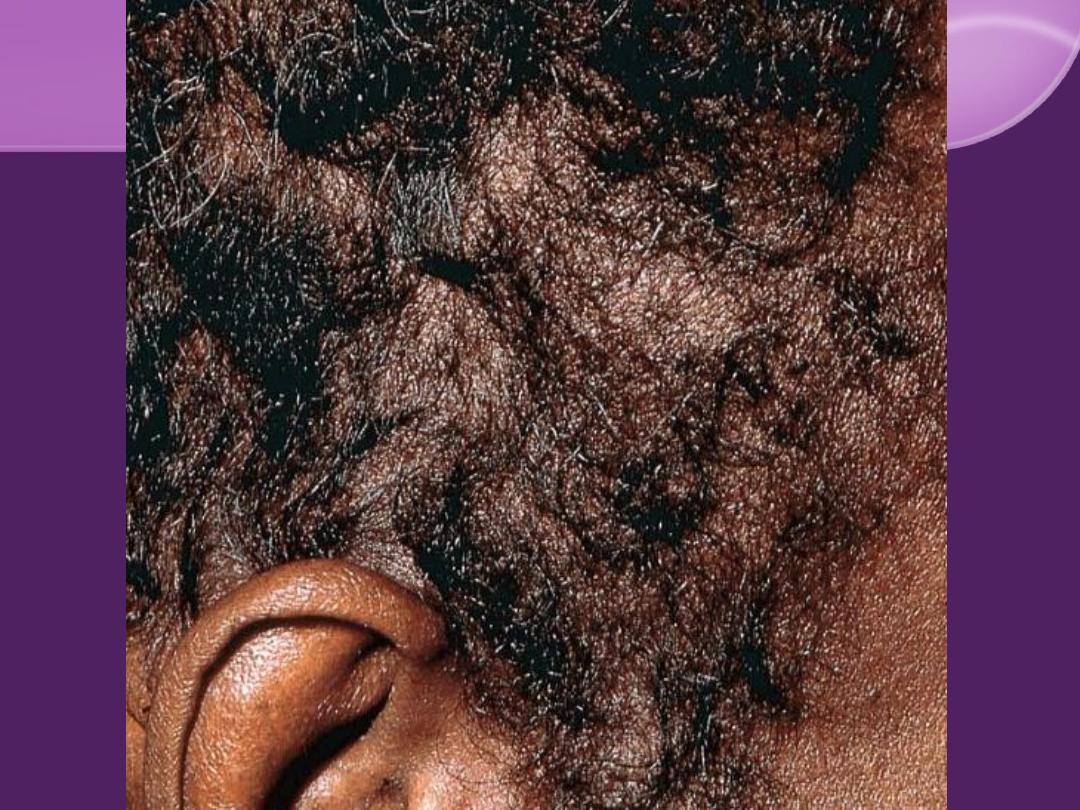

"Moth eaten" alopecia

Alopecia "Moth eaten"